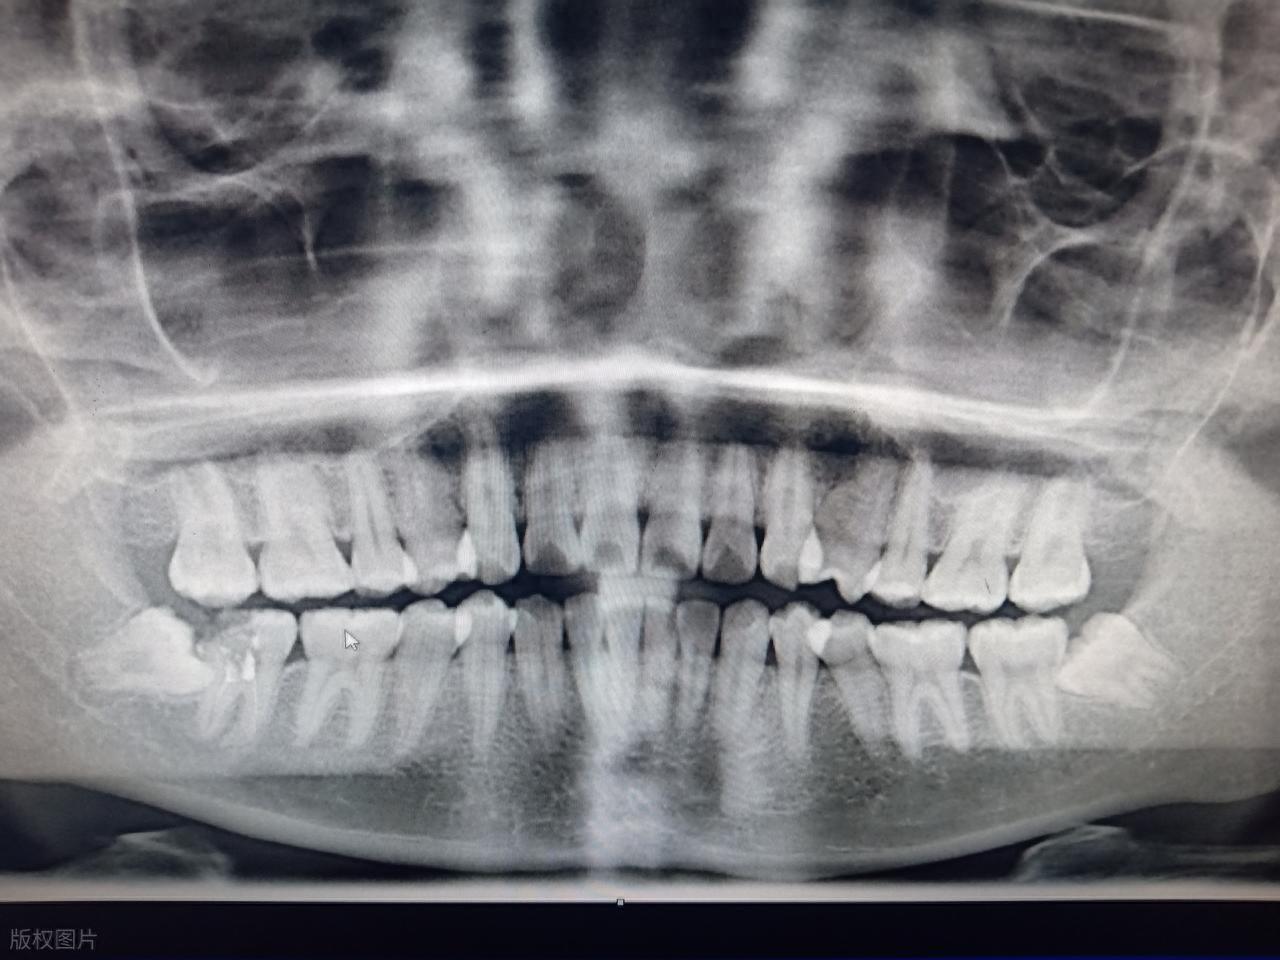

極少數情況下,橫着長的智齒完全埋伏在頜骨內,與鄰牙無接觸,無任何不適症狀,且通過影像學檢查顯示其生長位置穩定,不會對周圍組織造成潛在危害,這種情況下可以在醫生的指導下暫時觀察,定期複查。但需注意,觀察期間若出現任何不適,應及時就醫評估是否需要拔除。